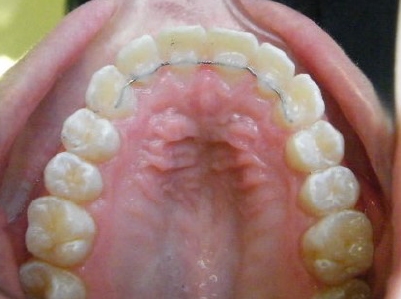

Patient 2: Significant increased overjet and upper and lower crowding.